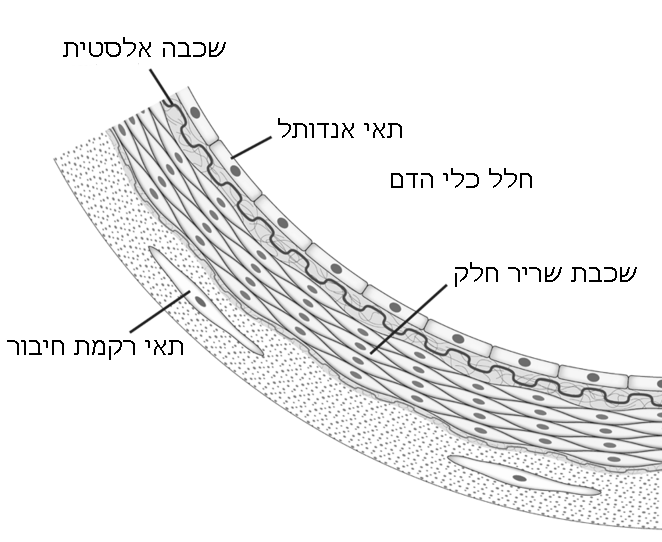

מחסום דם-מוח (brain blood barrier BBB) מצוי בכלי הדם המגיעים למוח.

זהו מבנה ("קרום") של תאי אנדותל המהווה את החיפוי הפנימי של כלי הדם, רק שבמוח הוא צפוף הרבה יותר וחדיר הרבה פחות.

תפקיד מחסום דם-מוח למנוע מעבר של כימיקאלים ותוצרים שונים המצויים במחזור הדם מלהגיע למוח ולגרום לו נזק.

את מחסום דם-מוח מסוגלים לעבור מולקולות מסיסות שומן וכן חמצן, פחמן דו-חמצני, הורמונים סטרואידים, אלכוהול וסוכרים.